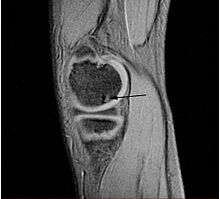

| A large flap lesion in the femur head typical of late stage Osteochondritis dissecans. In this case, the lesion was caused by avascular necrosis of the bone just under the cartilage. | |

Magnetic resonance imaging (MRI) is useful for staging OCD lesions, evaluating the integrity of the joint surface, and distinguishing normal variants of bone formation from OCD by showing bone and cartilage edema in the area of the irregularity. MRI provides information regarding features of the articular cartilage and bone under the cartilage, including edema, fractures, fluid interfaces, articular surface integrity, and fragment displacement.[36][37] A low T1 and high T2 signal at the fragment interface is seen in active lesions. This indicates an unstable lesion or recent microfractures.[29] While MRI and arthroscopy have a close correlation, X-ray films tend to be less inductive of similar MRI results.[37]